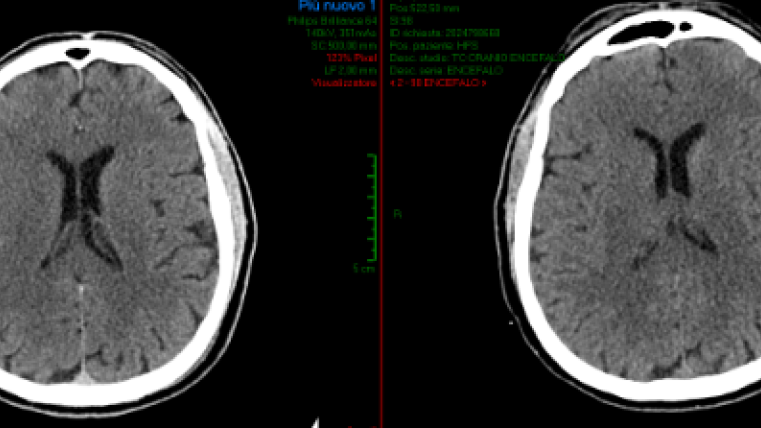

Le Tac di controllo post operatoria e a 24 ore hanno dimostrato subito una evoluzione favorevole del quadro a livello dell’encefalo, confermato anche clinicamente (Figura 5).